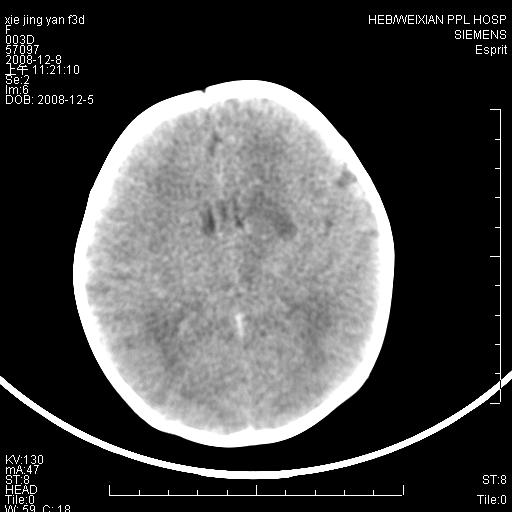

标题: PED1679:最小的“脑梗死”患者,能下其他诊断吗?

女,三天。呕吐,右侧上肢抽搐5小时。新生儿缺氧缺血性脑病有这样在基底节区出现缺血性表现的吗,并且有一侧肢体症状。

病灶局限,余脑质密度均匀,灰白质分界可.考虑脑梗死

新生儿缺血缺氧性脑病,左侧脑室旁脑白质软化

一侧肢体有症状,而且发生在灰质,边界较清晰。还是先考虑脑梗死!~!建议mri检查